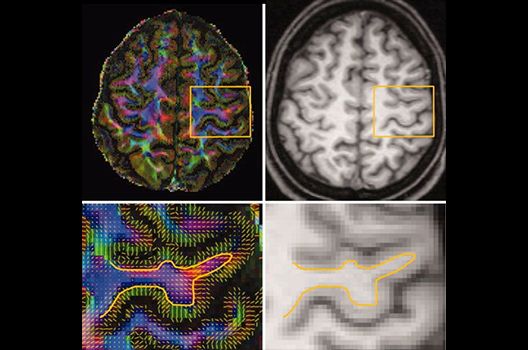

- MR-Diffusionstensorbildgebung (Faserbahndarstellung/fiber tracking)

Die Magnetresonanztomographie (MRT) ist ein Verfahren, bei dem durch magnetische Kräfte Bilder des Körperinneren angefertigt werden. In der Neuroradiologie können manchmal kleinste Veränderungen schwere Folgen haben; daher forschen wir an der Entwicklung hochauflösender MRT-Sequenzen, mit denen diese Prozesse und auch einzelne Nervenfaserbahnen sichtbar gemacht werden können. Darüber hinaus sind bei vielen Erkrankungen des Gehirns die Blutgefäße betroffen. Daher arbeiten wir an der Neu- und Weiterentwicklung von MRT-Sequenzen zur Darstellung der Blutgefäße und zur Blutflussanalyse (sog. „Angio-MRT“). Einen besonderen Forschungsschwerpunkt unserer Klinik stellen die MR-Protonenspektroskopie und die funktionelle MRT dar, mit denen die Analyse einzelner chemischer Substanzen im Hirngewebe oder die Darstellung ausgewählter Hirnfunktionen möglich ist.